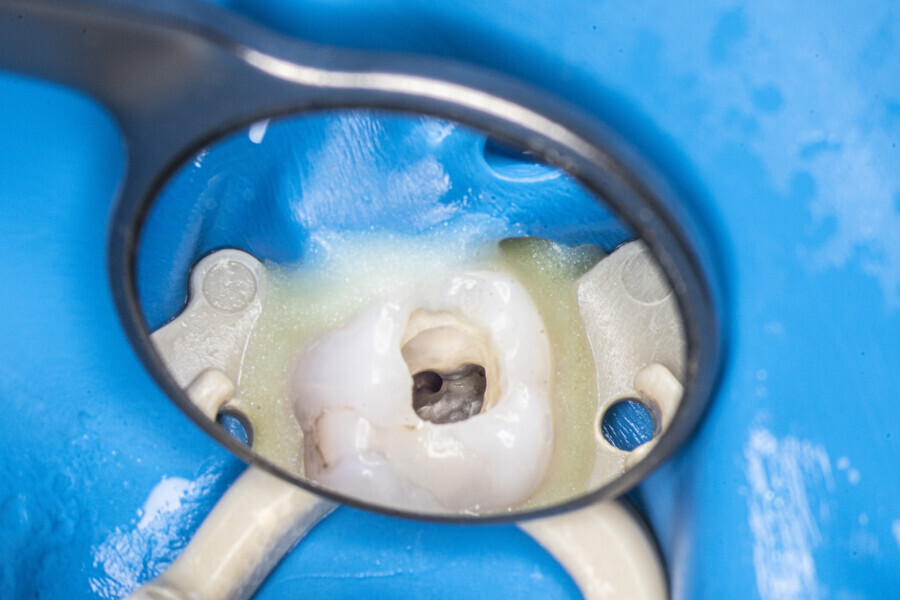

The first trials of the LPE concept were performed on extracted human molars. Although the dynamics of fluid during root canal irrigation are completely different in vivo than in extracted teeth, these kinds of trials provide initial information about the procedure. Some of these teeth had apices closed with a coat of wax and composite resin to close the apical delta and simulate the periapical tissue. After creation of the access cavity, the pulp chamber was cleaned with continuous irrigation with 5.25% NaClO activated with a SkyPulse laser (Fotona) in AutoSWEEPS mode (20 Hz, 15 mJ). A 25/0.07 reciprocating file (Shenzhen Perfect Medical Instruments) was used to perform the pre-flaring procedure. After opening the coronal third, continuous irrigation with 5.25% NaClO activated with the laser was used to clear the debris for 30 seconds. After removing the debris, a #10 C-PILOT file (VDW) was used to establish apical patency, without forcing the file if possible. In some cases, apical patency was reached already at this stage of root canal preparation. In all cases, the second step of instrumentation was the preparation of the middle third with the same file, and the same irrigation procedure was performed. Subsequently, the C-PILOT file was used to reach the apical foramen. At this stage, apical patency was reached in most cases, but in some roots, there was no possibility of entering the apical foramen. The working length was confirmed with a radiograph with the hand file. Usually, the next procedure to be done is apical preparation, but the LPE concept is based on an enhanced irrigation protocol. Following this protocol, irrigation was performed for 5 minutes with continuous flow of 5.25% NaClO activated with the SkyPulse laser in AutoSWEEPS mode (20 Hz, 20 mJ) with a conical sapphire fibre. The next step was alternating irrigation with 17% EDTA for 30 seconds, with 5.25% NaClO for 30 seconds and with 17% EDTA for 30 seconds, all activated with AutoSWEEPS, followed by irrigation for another 5 minutes with 5.25% NaClO activated with AutoSWEEPS. In most cases, the next step after this stage of enhanced irrigation was the calibration of the apical constriction rather than apical preparation per se, but this step requires further investigation.

At the first appointment, both teeth were opened, the old restorations were removed, all the root canal orifices were located and the first mesiobuccal (MB1), distobuccal (DB) and palatal canals were shaped. In both teeth, the MB2 orifices were located, but the canals were not shaped. The preparation phase was similar to that explained earlier. During the root canal preparation phase, the hand file was used to establish patency after each reciprocating instrument, and the canals were flushed with NaClO activated with the SkyPulse laser in SWEEPS mode for 10–15 seconds. After reaching two-thirds of the estimated working length with the reciprocating files, the LPE enhanced irrigation protocol with the SkyPulse laser was employed. The apical preparation was not performed at this stage. Owing to a lack of time at this appointment, the canals were flushed with EDTA and sterile water, and a 2% solution of chlorhexidine was poured as an intra-canal dressing. Both teeth were closed with temporary composite restorations.

At the second appointment, the temporary restorations were removed, and the chlorhexidine was washed out with sterile water and EDTA. After opening the orifice of the MB2 canal in the first molar, the operator was not able to reach patency in the canal. Therefore, the isthmus between the MB1 and MB2 orifices was opened with diamond-coated ultrasonic tips. Finally, patency was reached. Shaping the MB2 canal in the second molar was possible only to the place of the junction with the MB1 canal. The CBCT imaging had revealed previously that the MB2 canal should have its own lumen in the apical third, but the place of the junction was below the curvature. The possibility of locating this space without damaging the root was very poor. At this stage, the LPE enhanced irrigation protocol was performed again. After performing of the irrigation protocol, the apical preparation was performed for all the canals. The final irrigation protocol was performed with 5 minutes of constant flow of 5.25% NaClO for 2 minutes, alternating with 17% EDTA for 30 seconds, with 5.25% NaClO for 30 seconds and 17% EDTA for 30 seconds, and irrigation with 5.25% NaClO for 5 minutes. All the irrigants were activated with an EDDY sonic tip (VDW). After performing the periapical radiographs, a CBCT scan was performed to confirm the separate path of the sealer that filled previously unprepared spaces of the MB2 canals in both teeth. In both cases, it was clearly visible on the CBCT image that all the previously unprepared spaces were filled with the obturation material.

A 25-year-old female patient presented to the office owing to constant pain related to the mandibular left first molar. Pulp necrosis was diagnosed. After the emergency appointment, the patient was referred for complete treatment. The tooth was treated in the same manner as described in the previous paragraphs. After creation of the access cavity, the orifices were located. In the root chamber, the orifices of the MB, mesiolingual, DB, distomesial and distolingual canals were present. After pre-flaring and preparation of the middle third, the LPE enhanced irrigation protocol with the SkyPulse laser was performed. After the irrigation protocol in the mesial root, the irrigants started to flow between lingual and buccal canals. Such an observation suggested to the operator that some space in the isthmus had been created. It is worth mentioning that at this stage apical enlargement was not performed. Final preparation of all five canals was performed with the reciprocating file, and the final irrigation protocol was performed as in the previous case. The radiograph clearly revealed that the isthmus space was filled with the sealer. The radiograph and CBCT image revealed that there were four portals of exit in the mesial root.

A 30-year-old female patient presented to the office owing to pain related to the maxillary right first molar. The radiograph revealed a periapical radiolucency, indicating exacerbated chronic periapical periodontitis. The access cavity was created with the Safe Access and Preparation Concept burs set (manufacturer). The pulp chamber was cleaned with 5.25% NaClO activated with the SkyPulse laser. Four orifices were located, and all four canals were shaped in the same sequence described previously. The LPE enhanced irrigation was performed with activation by the SkyPulse laser. In the mesial root, a clean isthmus was visible, and the irrigants started to flow between the MB1 and MB2 canals in the apical third, which was confirmed with a micro-suction cannula. In the MB1, MB2 and DB canals, apical preparation was performed with Endostar E3 Azure files (Poldent) up to size 25/0.04 owing to the apical curvatures. In the DB canal, patency was not established. The final irrigation protocol was performed in the same sequence as described before. The periapical radiograph confirmed that the isthmus was filled with the sealer.

A 35-year-old female patient was referred to the office owing to the lack of patency in the pulp chamber. The periapical radiograph and CBCT image confirmed that the pulp chamber was completely calcified. The calcification of the pulp chamber was removed with diamond-coated ultrasonic tips. After removing the calcification, four orifices were located and shaped in the sequence described previously. The LPE enhanced irrigation protocol with the SkyPulse laser was performed. In this case, the MB2 canal joined the MB1 canal approximately 4 mm before the apex and was shaped only to this length. Apical preparation and irrigation were performed as described previously. The periapical radiograph revealed that the MB2 canal had a separate apical part, which was cleaned with the irrigants and filled with the sealer, and that the palatal canal had two portals of exit.

The in vitro trials and in vivo cases, periapical radiographs and postoperative CBCT images demonstrate that the laser activation of irrigants allows the clinician to achieve much better removal of the hard-tissue debris than with the conventional irrigation methods. The LPE concept appears promising in terms of the improved removal of hard-tissue debris. It is important to mention that this is only a clinical observation. The most important part of this observation is a very rapid flow of the irrigants between the root canals located in the same root after the LPE enhanced irrigation protocol with the SkyPulse laser but before apical preparation.